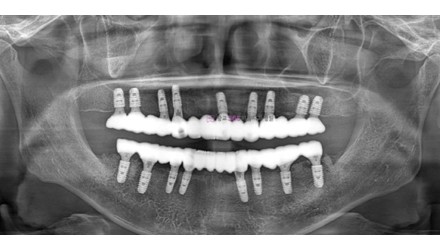

박*수 임플란트 시술 사례

전체 임플란트

20**.**.**

치료 전

치료 후